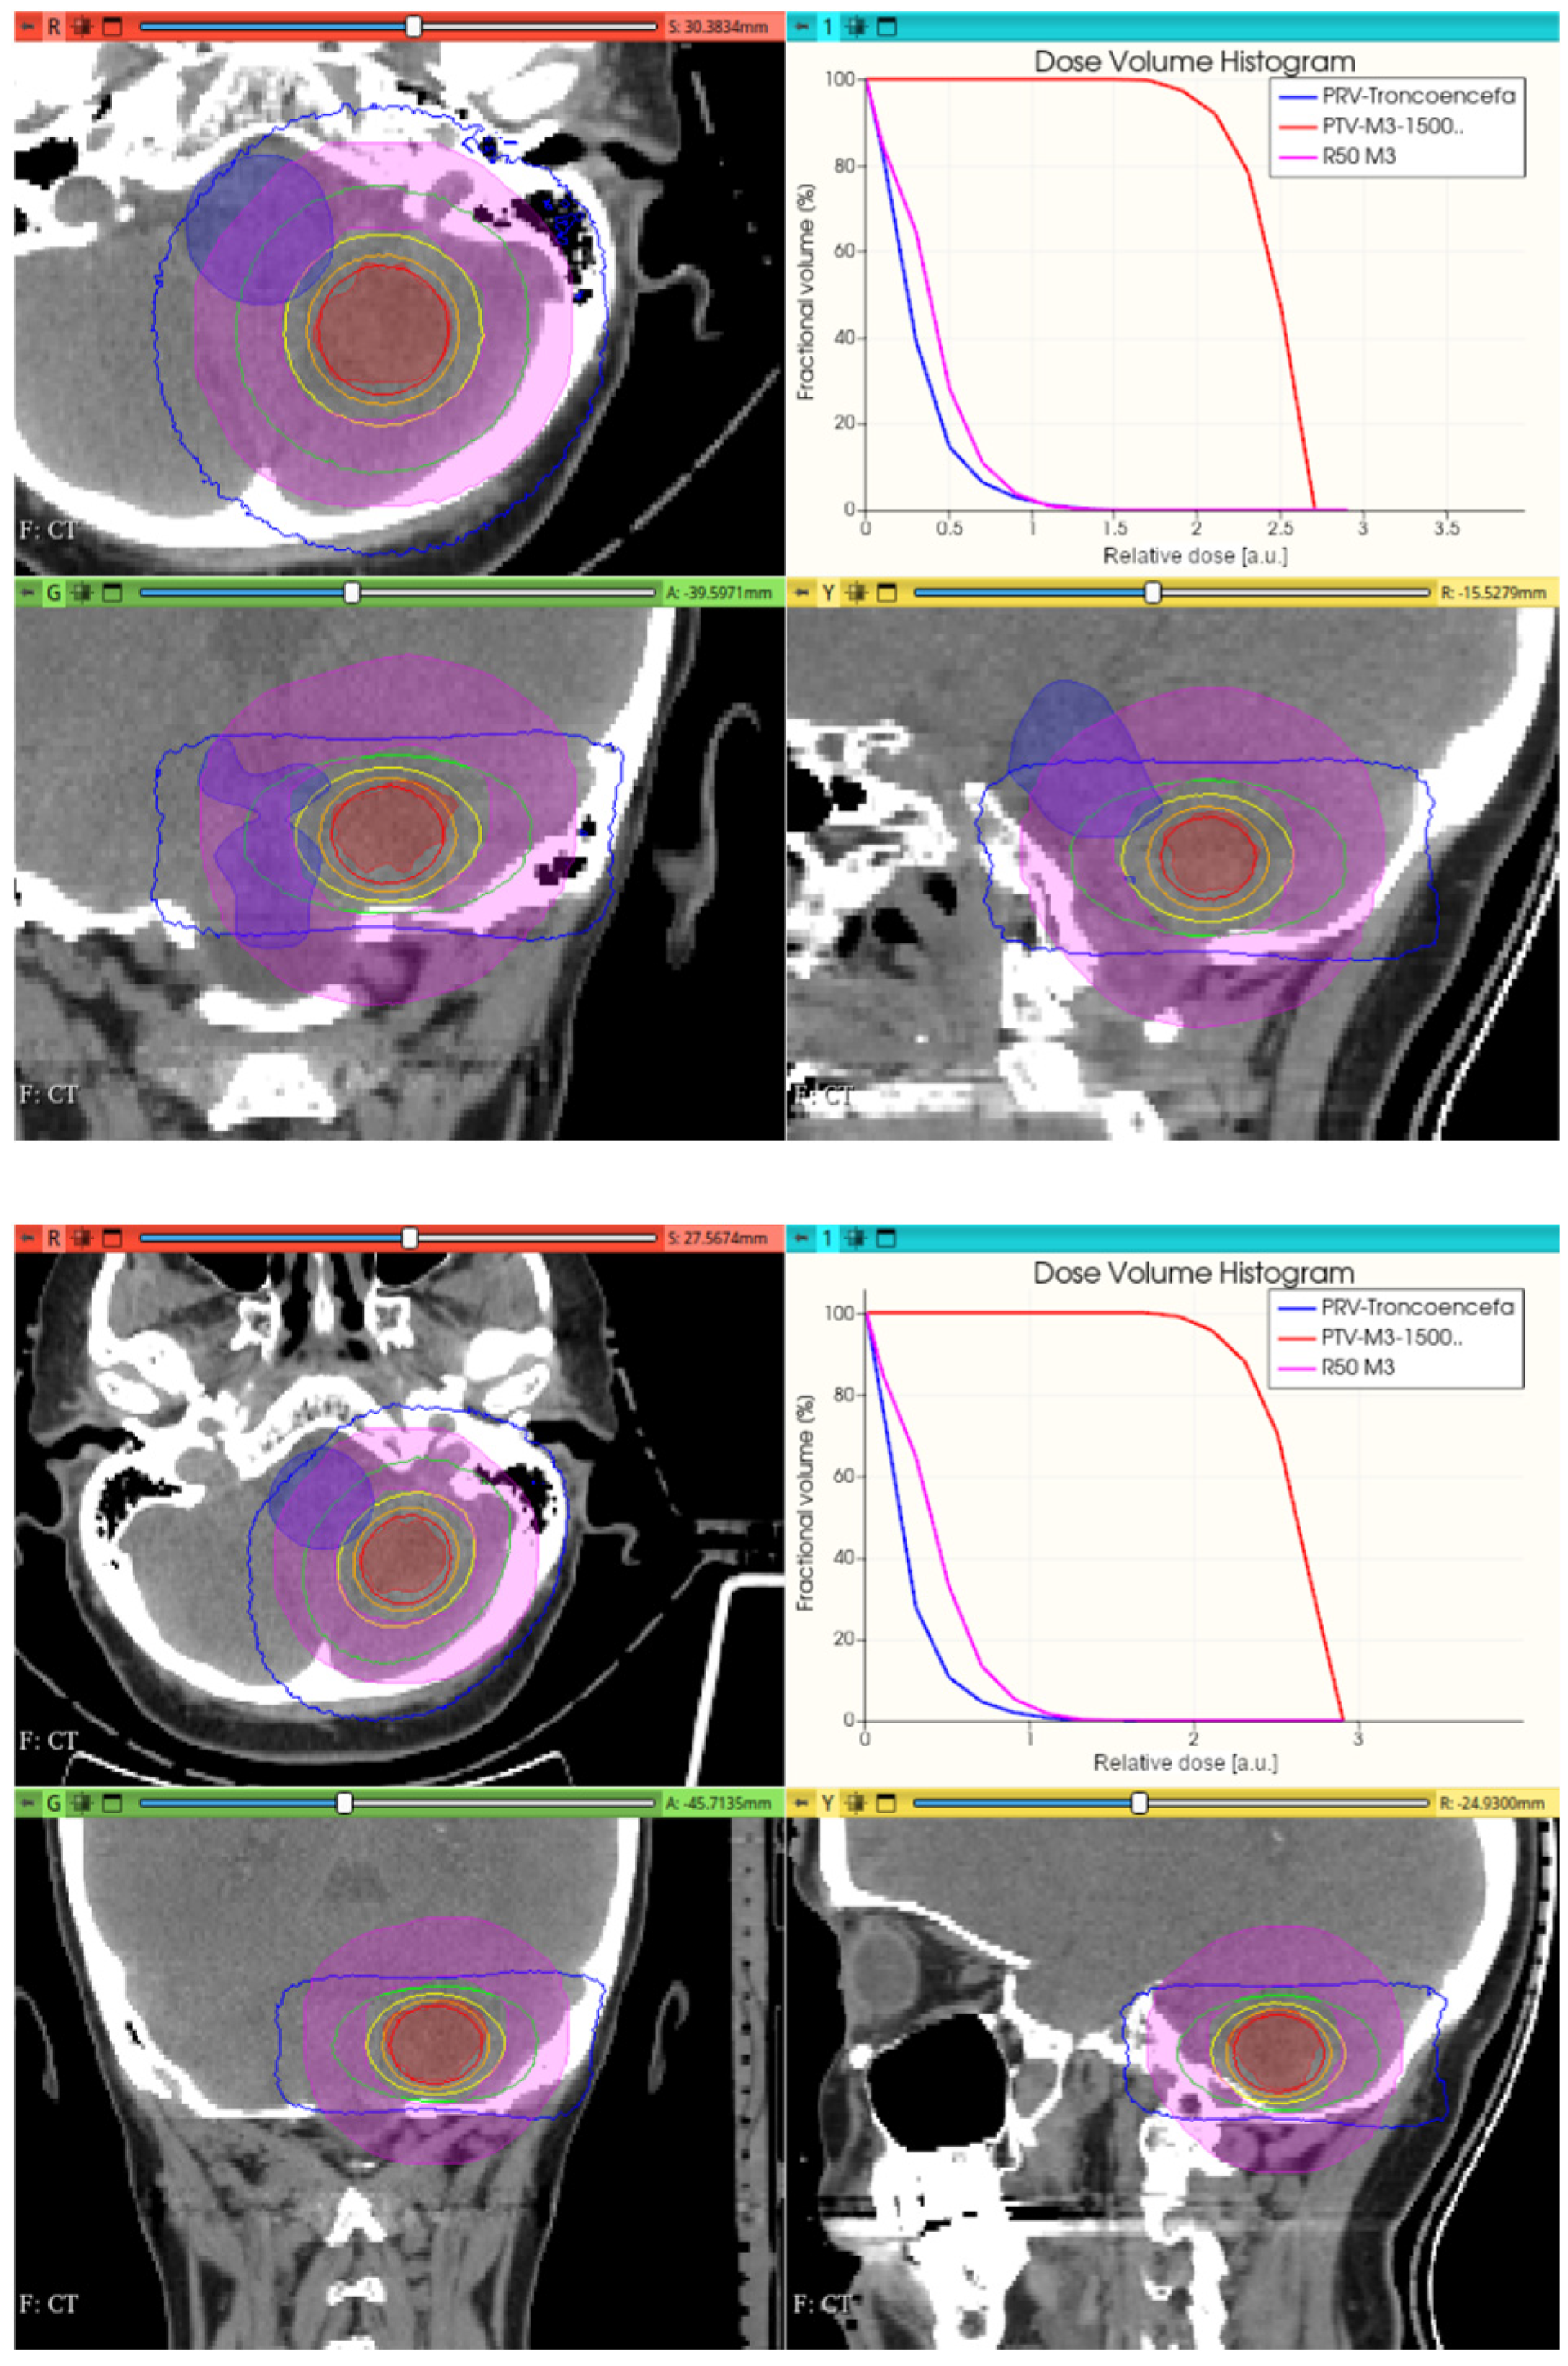

3.3.1. Preliminary CONVERAY Dosimetry Performance for Intracranial Irradiations